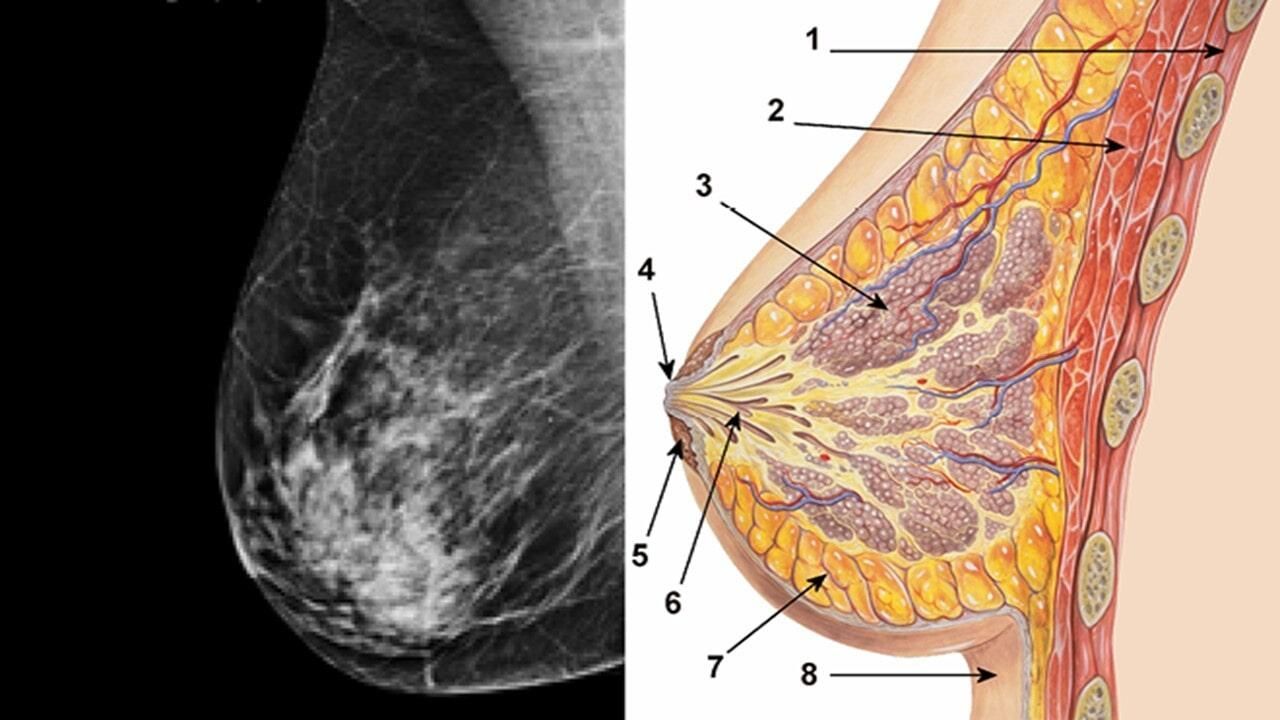

En el cuerpo de la mujer, desde la adolescencia se desarrollan los senos, donde se ubican las glándulas mamarias, las cuales están involucradas en la producción de leche particularmente después del embarazo. Esta parte del organismo está compuesto por lóbulos y lobulillos, conectados a través de conductos, y se encuentran en tejido adiposo.

Normalmente y de manera cotidiana, se generan las células del organismo, estas se desarrollan y mueren de manera ordenada; sin embargo, cuando se rompe ese orden y hay un crecimiento anormal se producen tumores, que pueden ser malignos o benignos.

Los tumores cancerígenos son de distintos tipos, pero la mayoría tienen un común denominador, que es el crecimiento anormal de las células malignas que se encuentran en el tejido mamario.

Entre los principales tipos que existen destacan los siguientes:

· Carcinoma ductal in situ

· Carcinoma ductal infiltrante (o invasivo)

· Carcinoma lobular in situ

· Carcinoma lobular infiltrante (o invasivo)

· Carcinoma inflamatorio